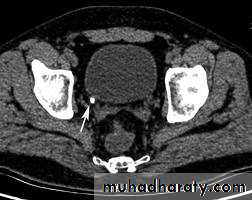

CT scans used in some hospitals during acute renal stone-Non contrast CT sensitively identify calculi and non opacified collecting system down to the level of obstruction. it has a sensitivity of 97% and specificity of 96% for detection of ureteral calculi

- Over 90% of calculi are radiopaque on plain films and virtually all on CT as very sensitive for detection of calculi, even those that appear radiolucent on plain film.- Most of these stones are a mixture of calcium oxalate and phosphate.